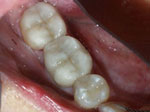

Onlays

Before  After

What's an Onlay?

It's a dentist-fabricated replacement of one or more cusps of your tooth. Dr. Mirmiran provides this valuable service because she feels that they are much more conservative than a full crown.

Porcelain Onlays are beautiful, feel as natural as your own tooth, and last 15-20 years.